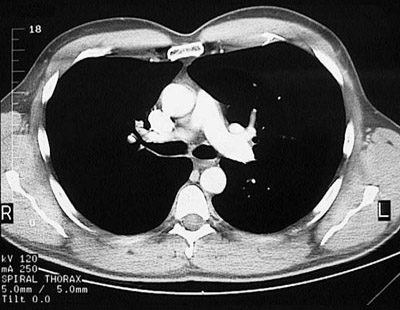

[T6] This is a normal chest CT scan demonstrating the right lung and left lung and pectoralis major muscle and superior vena cava and pulmonic trunk and right pulmonary artery and aortic root and sternum and descending aorta and azygous vein and right main bronchus and carina and left main bronchus and subscapularis muscle and spine of scapula and infraspinatus muscle and trapezius muscle and sacrospinalis muscle and transversospinal muscle in the upper chest.